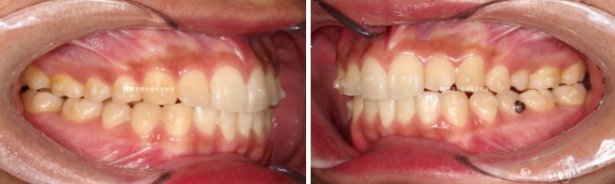

23.12

1년 전 인비절라인 교정을 위해 내원하신 환자분입니다.

삐뚤한 앞니가 보입니다.

파란 화살표 어금니는 아래 어금니와 거꾸로 물리는 반대교합 입니다.

23.12~24.10

파란 화살표 반대교합도 해소가 되었습니다